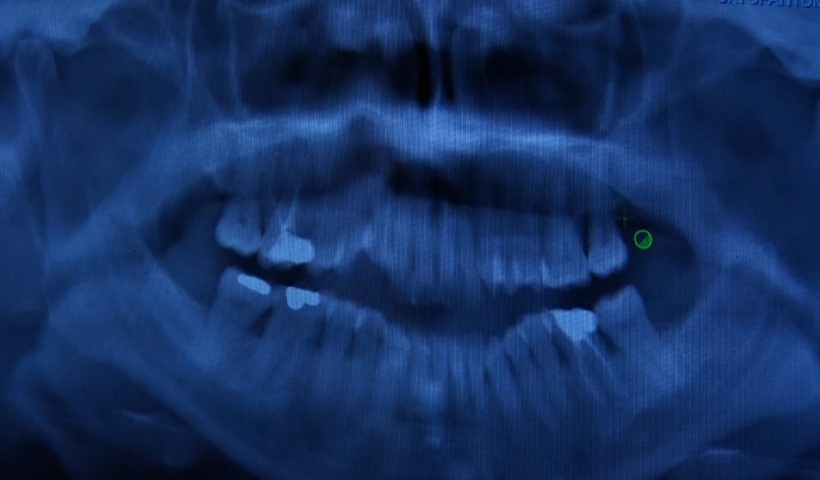

Diş eti problemlerine dikkat, uzmanlar uyarıyor: "Sessiz ilerler"

Ağız ve diş sağlığında koruyuculuğun önemine vurgu yapan uzmanlar, diş eti hastalıkları ve neden olabileceği problemlere karşı uyarılarda bulundu. Vatandaşların çoğu zaman kanama, ağrı gibi belirtileri önemsememesinin daha ciddi problemlere neden olabileceğini aktaran Sarıyer Ağız ve Diş Sağlığı Merkezi Periodontoloji(Diş Eti Hastalıkları) Bölümü’nden Uzm. Dt. Ebru Özkan Bütün, sürece ilişkin bilgi verdi.

Uzm. Dt. Ebru Özkan Bütün, "Sağlıklı dişler sağlıklı bir zemin üzerinde var olabiliyor. Diş eti rahatsızlıkları genelde sessiz ilerler. Bize hastalar bir ağrı şikayetiyle değil de daha çok diş etlerinde kanama, diş sallanması ya da diş eti çekilmesi olduğu zamanlarda başvurur. Hatta randevularımızın çoğunu başka diş hekimlerinin yönlendirmesiyle durumun farkına varan hastalar oluşturmakta. Oysa bahsettiğim başvuru nedeni olan o şikayetler hastalığın ileri aşamalarını gösteriyor. Bu nedenle erken teşhis ve tedavi koymak için rutin kontroller diş hekimliğinde çok önemli. Tedavi süreci kişiye özel bizde basit bir diş taşı temizliğiyle de sorunu çözebiliyoruz ama bu ileri cerrahi aşamalara kadar da ilerleyebiliyor. En önemli nokta; kişinin evde uyguladığı ağız hijyeni uygulamaları, rutini. Her zaman söylüyoruz; günde en az 2 kere diş fırçalama, diş ipi kullanımı veya ara yüz fırçası kullanımı, düzenli kontrolleri aksatmamak altın standart. Bunlara uyulduğu sürece durum da kontrol altında olacaktır" dedi.